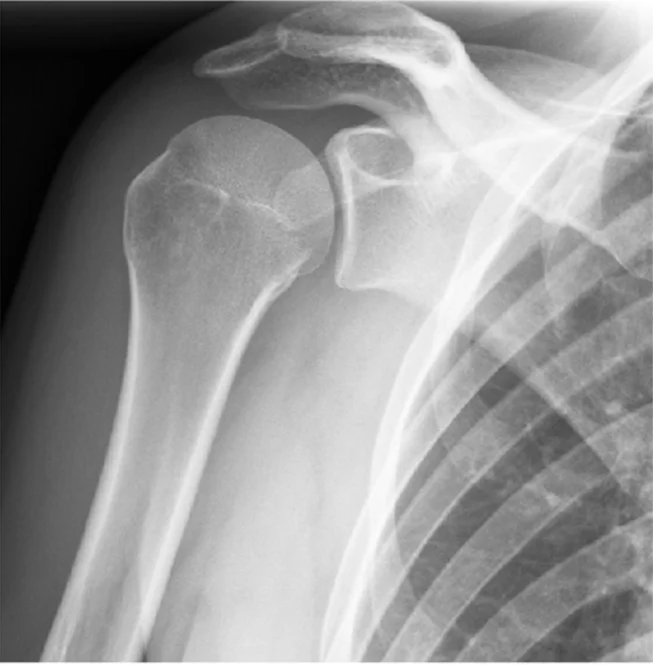

bone alignment

- subluxation of patella

- Anterior dislocation of shoulder joint

Bone and Joint Alignment